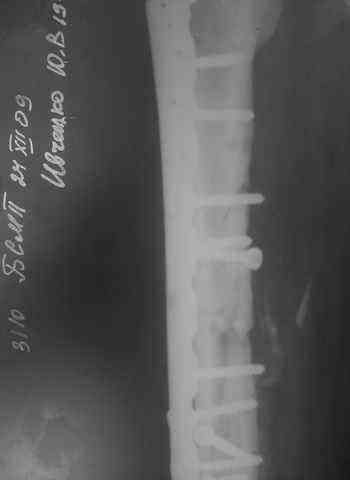

Несрошийся открытый фрагментарный, оскольчатый, перелом в/с/3 правого бедра с размозжением мягких тканей. Состояние после ПХО,МОС,ВО ЧКФ стержневым АВФ. 10.10.09.Заживление раны per prima. Операция:16.12.09,открытый накостный МОС,аутокостная пластика(из крыла подвздошной кости)правого бедра. После п/о периоде заживление раны вторичным натяжением (на 5-е сутки распущены швы, после очищения раны наложины вторичные швы) На этапных RO-гр:остеолизис костного трансплантата и дистального фрагмента перелома бедра. Вопрос:дальнейшая тактика лечения-БИОС аутокостная пластика (трансплантат на сосудистой ножке М/Б кости). Билокальный остеосинтез по Илизарову с остеотомией подвертельной и надмыщелковой области бедра. Мозможен ли аутотрансплантат без сосудистой ножки? Чем улучшить васкуляризацию? Декортикация? Тактика выжидания остеолизиса, а затем оперативное лечение.